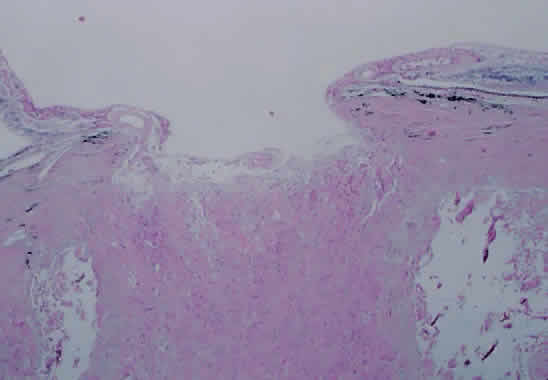

Production of aqueous humor is vital for the continued health of the ocular structures. Aqueous provides the necessary intraocular pressure that allows the eye to maintain its shape and provides nutrition for the nonvascular corneal endothelium and lens epithelium. Inflammation of the ciliary body, as in acute or chronic iridocyclitis, may result in a decrease in aqueous production and thus the characteristic finding of reduced intraocular pressure. In vivo studies of the human ciliary body during acute anterior uveitis show an enlarged cross-sectional area and occasional epithelial cyst formation.153 Pathology of the ciliary body in cases of chronic feline uveitis shows infiltration with chronic inflammatory cells,154 findings that are typical for human cases as well. Continued inflammation in the eye may result in the formation of a fibrous membrane stretching from ciliary process to ciliary process, across the retropupillary space (Fig. 23). Contraction of this fibrotic cyclitic membrane may result in ciliary body detachment with decreased production of aqueous humor, eventually leading to chronic hypotony if the process is not reversed.

Fig. 23. Ciliary body region of eye showing a fibrous membrane emanating from the ciliary processes (arrows). This membrane reached across to the ciliary processes on the opposite side of the eye. Bone formation can be seen at the lower portion of the figure (arrowhead) (hematoxylin and eosin; × 31).